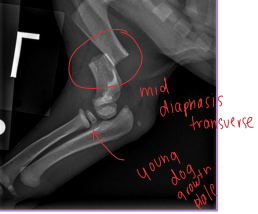

Salter-Harris = Physeal Fractures

Common in young animals (open physes)

Physeal fractures

Young animals, open growth plates

Diaphyseal Fractures

Transverse: plate + screws, IM pin